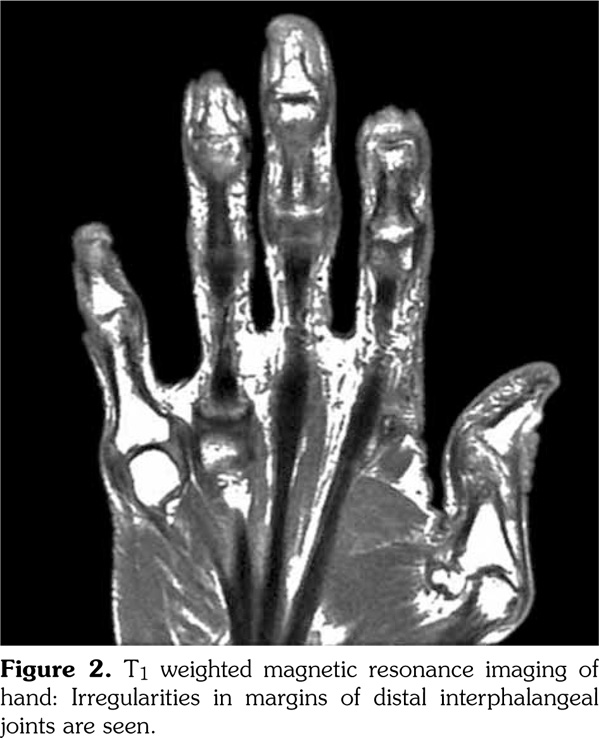

A complete blood count, electrolyte, and acute phase reactant tests revealed no abnormalities. Rheumatologic markers including the rheumatoid factor and anti‐citrullinated antibody were all negative. Direct radiography revealed an evidence of intraarticular erosion, periosteal reaction, and prominent thickened periarticular and paraosseous soft tissues (Figure 1). A magnetic resonance imaging of the hands showed irregularities of the DIP joints in T1 weighted images (Figure 2). Based on the findings mentioned above, the patient was diagnosed as having POPP. The patient was started on methylprednisolone 5 mg/day and methotrexate 10 mg/week, which increased to 15 mg/week after two weeks. The patient was evaluated after four weeks of treatment and liver function tests; the creatinine and complete blood counts were normal and there was an 80% improvement in the pain scores (10 cm visual analog scale) for arthralgia. The patient was re‐ evaluated after three months of treatment and there was a 90% improvement in the pain scores compared to the scores at admission and new nail formations at the base of the nail beds were observed.